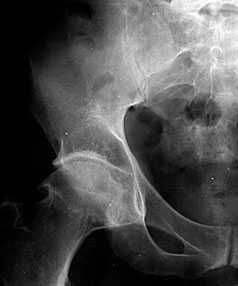

В начальных стадиях (1-2 стадии по Kellgren) ОА тазобедренных суставов при рентгенологическом исследовании определяются: незначительное сужение суставной щели, слабовыраженный субхондральный остеосклероз, точечные кальцификаты в области наружного края крыши вертлужной впадины (зачаток остеофитов), заострение краев ямки бедренной головки в области прикрепления круглой связки бедренной головки (рис. 1).

Рис. 1. Обзорная Rо-графия тазобедренного сустава в прямой проекции.

Деформирующий остеоартроз II ст. по Kollgren. Крупные остеофиты на краях суставных поверхностей. Грибовидная деформация бедренной головки

В поздних стадиях заболевания (соответствует 3-4 стадии ОА по Kellgren) отмечаются:

• прогрессирующее сужение суставной щели

• формирование различной формы и размеров остеофитов на краях суставных поверхностей вертлужной впадины, бедренной головки, отчего она со временем приобретает грибовидную форму. В средней части вертлужной впадины возможно формирование клиновидного остеофита, который может обусловить латеральное смещение бедренной головки

• углубление вертлужной впадины может быть связано с развитием остеофитов; протрузия ее возможна на фоне остеопороза или истончения костей, составляющих дно вертлужной впадины

• выраженный субхондральный остеосклероз. Проявляется в первую очередь в области крыши вертлужной впадины, затем в верхнем отделе бедренной головки

• в далеко зашедших случаях - уменьшение в объеме и уплощение суставной поверхности бедренной головки на фоне выраженной кистовидной перестройки костной ткани, чередующейся с участками субхондрального остеосклероза. Костные кисты могут быть единичными или множественными. Возникают они в верхней части вертлужной впадины или в зоне наибольшей нагрузки на суставную поверхность бедренной головки

• асептический некроз бедренной головки

• подвывихи бедренной кости чаще вверх и латерально, реже вверх и медиально

• уплотнение костной ткани и укорочение шейки бедренной кости.